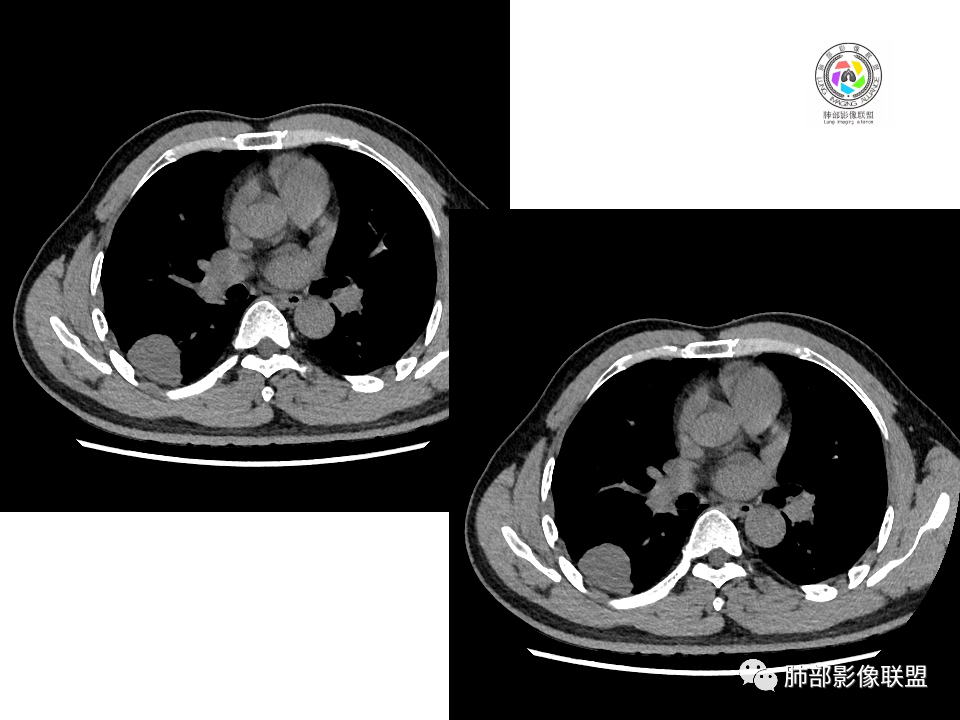

右肺中叶病灶

GGO,与支气管关系密切

这个形态、与支气管关系,与前两个不一致,所以考虑独立炎性病变。

3.右肺中叶外侧段胸膜下散在小片影,磨玻璃密度为主,边界不清,支气管相关。符合炎性特征!

5.慢性感染灶。缺乏临床表现,强化不显著会想到继发性肺结核,背段病灶过于光整均匀,周边过于干净使人狐疑,且“成掎角之势”的中叶病灶结核灶特点也着实不多。

有老师分析,多发病灶有磨玻璃晕,可以符合隐球菌感染,确实如此。但背段边缘如此锐利的块影还是更容易让人联想到新生物。